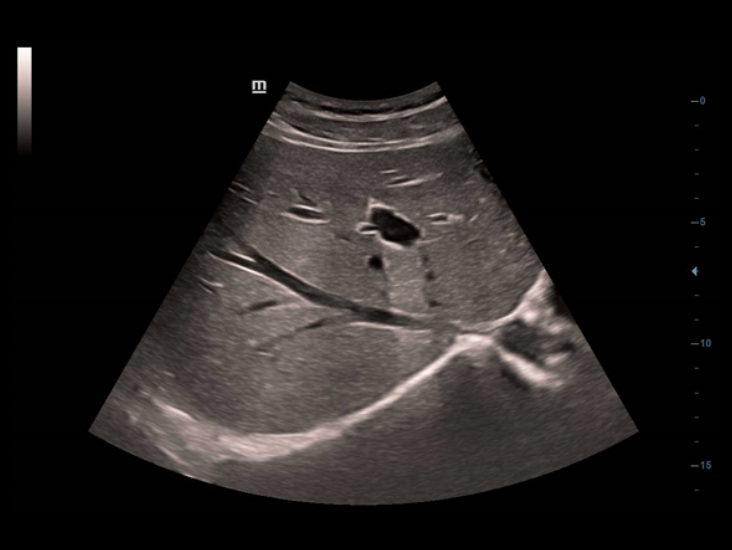

Hervorragende Detailaufl?sung

Unsere Motivation bei Mindray ist es, die moderne Medizintechnik durch zukunftsorientierte Techno-logien zu verbessern. Mit seinem Full HD-Monitor, bew?hrten Ultraschalltechnologien und einer optimierten Schallkopf-Familie bietet das DC-40 mit Full HD eine hervorragende Bildqualit?t. Sie verbessert ein breites Spektrum klinischer Anwendungen.

Diese bew?hrten Ultraschalltechnologien sorgen f├╝r eine h?here Diagnosequalit?t:

- iClear (Rauschunterdr├╝ckungs-Technologie)

- PSH (Harmonic Imaging mit Phasenverschiebung)

- iBeam: (Spatial-Compounding)

Der Einsatz anerkannter Bildgebungstechnologien macht das DC-40 mit Full HD sehr leistungsstark und hochwertig. Sie sind erfolgreich aus etablierten Ultraschallsystemen migriert worden. Eine clevere Kombination von Ultraschallsonden mit spezialisierten Schallk?pfen unterst├╝tzt erstklassige Ergebnisse in einem breiten Anwendungsspektrum. Mit Hilfe der Breitband-Schallk?pfe l?sst sich eine Vielzahl an Patiententypen erfolgreich untersuchen.